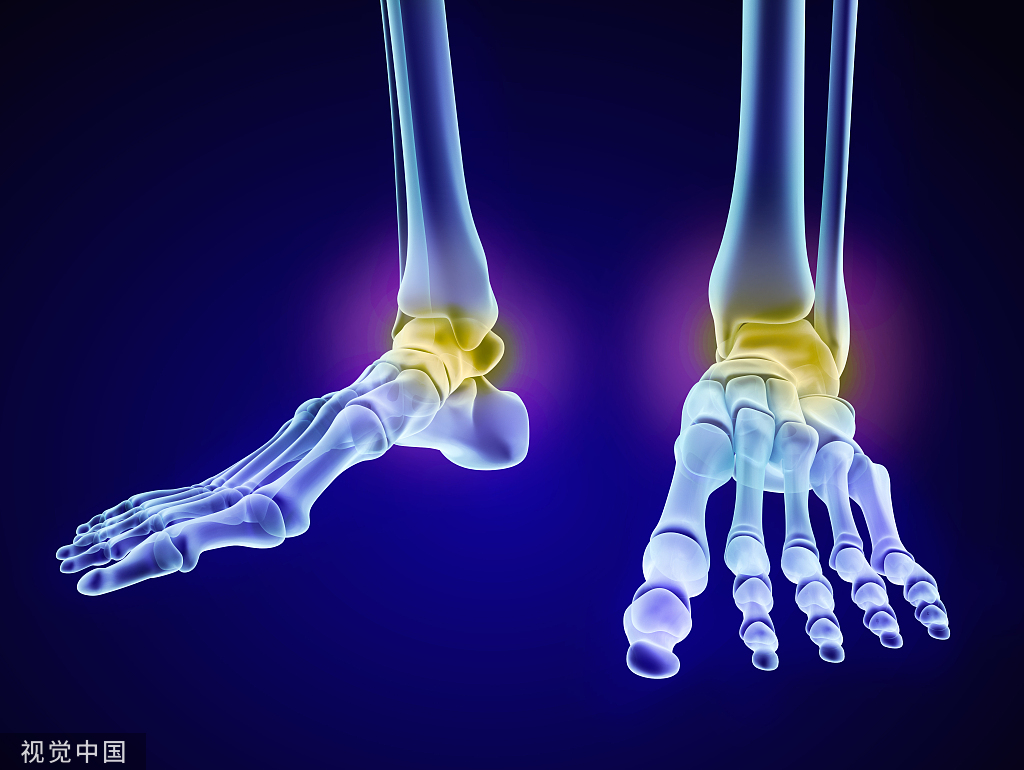

髋臼缺损-多孔钽

在髋关节翻修过程中大约25%的患者要单独翻修髋臼假体,而大约50%的患者要同时翻修髋臼假体和股骨柄。髋臼假体翻修时常常会遇到髋臼的骨缺损,如何合理处理髋臼骨缺损从而获得正常的髋关节旋转中心和髋臼假体的初始稳定性是一个棘手的难题。髋臼缺损的重建在全髋关节置换术(THA)中是具有挑战性的。实现假体的压合、骨缺损的桥接和髋关节旋转中心的恢复是成功翻修手术的目标。

为了实现这些目标,采取了不同的策略。对于有小缺损的患者,使用合适的外壳可以获得足够的稳定性。巨型部件可用于实现较大椭圆缺陷的稳定性。其他策略包括使用同种异体移植物与骨水泥壳、环或cage、高旋转中心的壳。然而,初级稳定性不足和宿主-骨接触小于50%会阻碍骨固定并导致早期失败。多孔钽金属(TM)的替代新技术已被证明是翻修THA中髋臼大缺损重建的可靠方法。这些植入物具有高孔隙度;摩擦系数高;弹性可与软骨下骨相媲美。多孔钽增强物是结构同种异体移植物的良好替代品,因为它们能够提供生物固定,重建容易,并且可靠地抵抗骨折或失败。